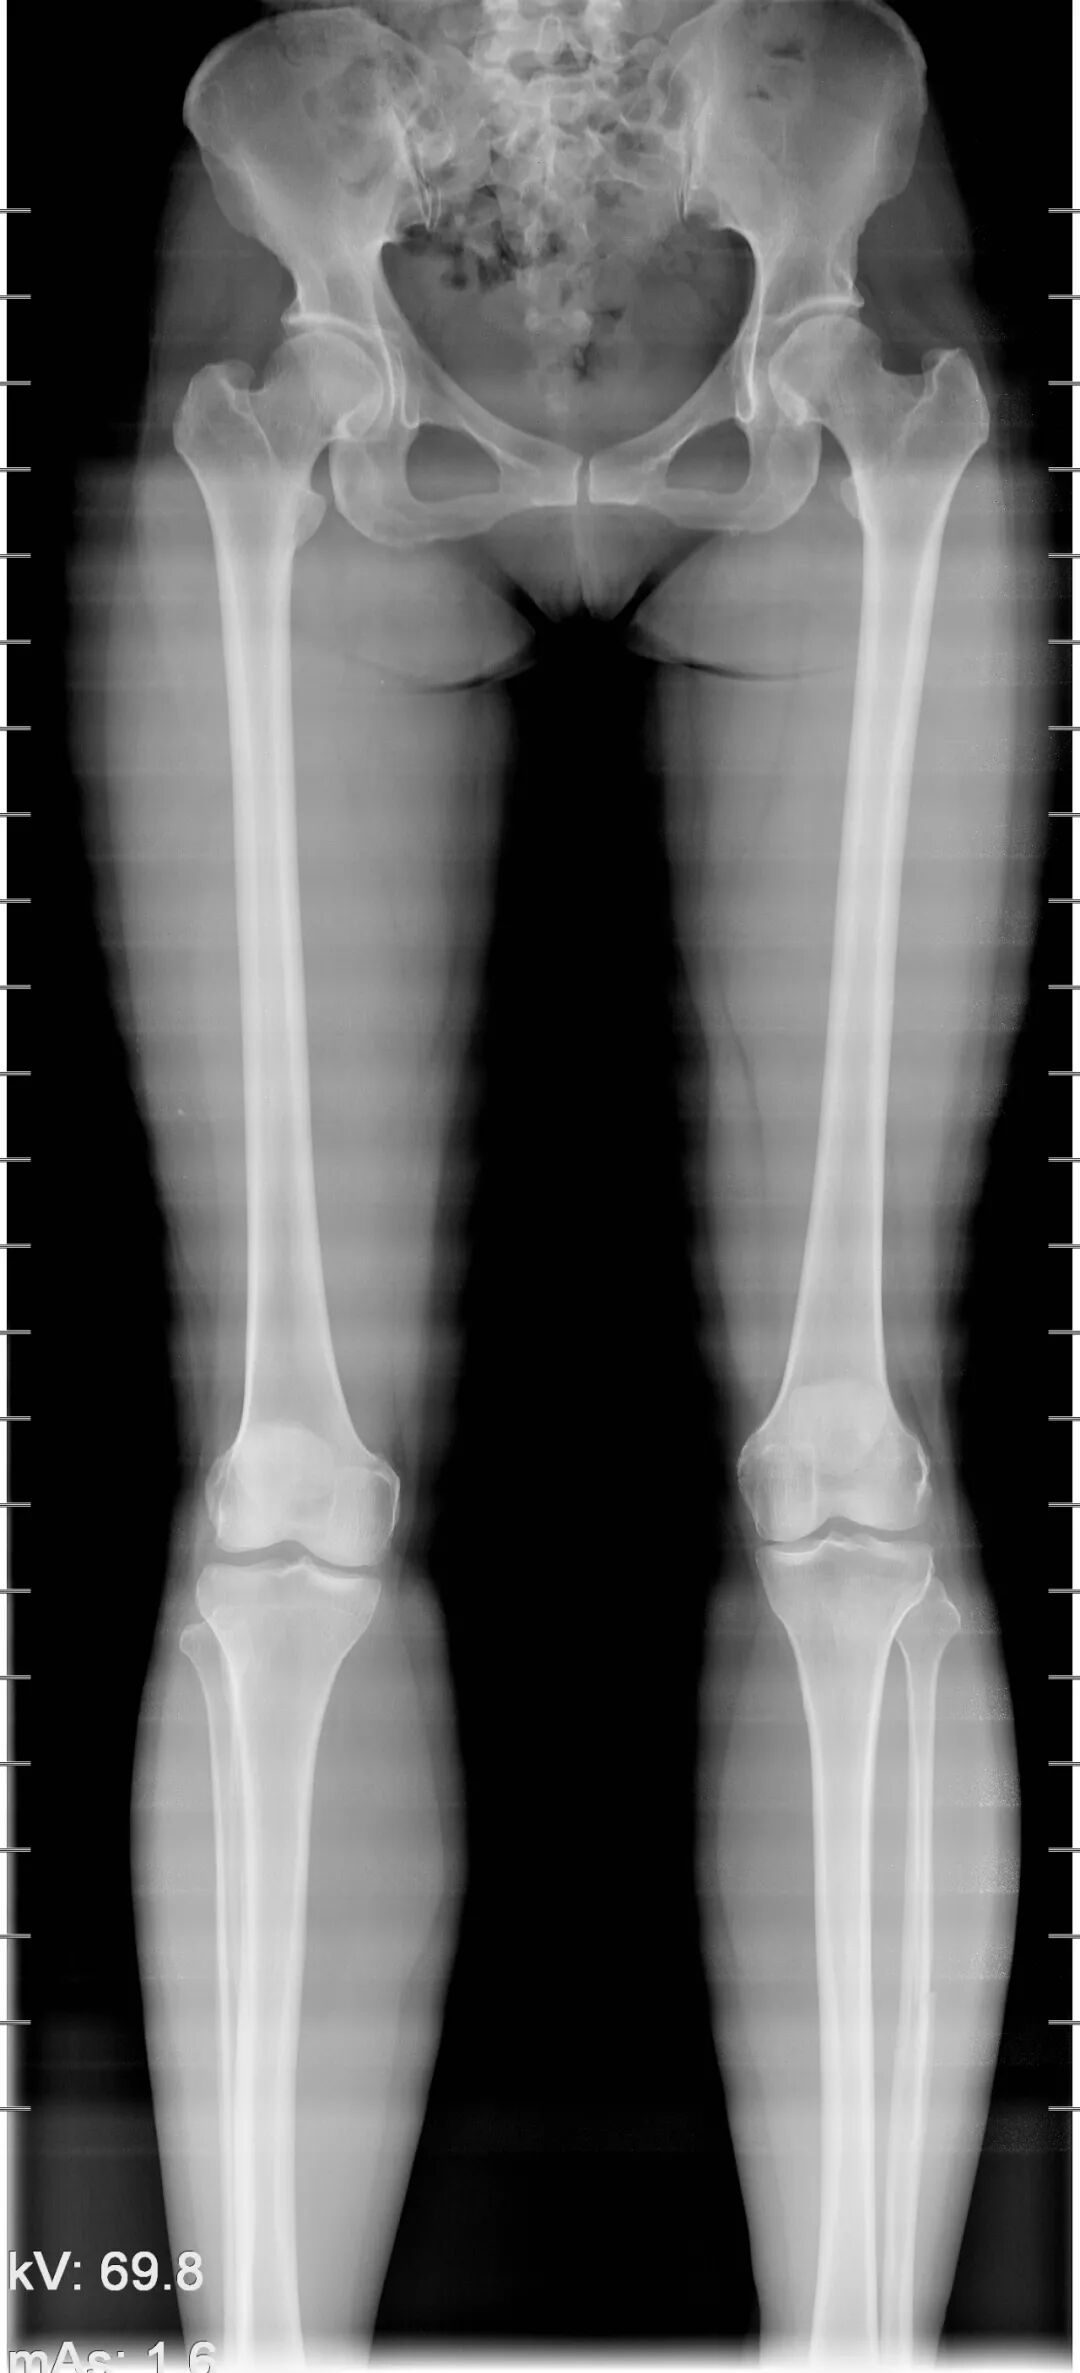

该设备属于多功能X线机,除具有传统数字胃肠机所有功能外,还有DR平板探测器X线摄影所有功能,主要用于消化道气钡双重对比造影、全脊柱拼接摄影、全下肢拼接摄影、ERCP、泌尿系造影、“T”管造影、钡剂灌肠、四肢造影、子宫输卵管造影等各类检查,是检查消化道溃疡、肿瘤、异物等疾病的主要方法之一。

在全脊柱拼接摄影、全下肢拼接摄影方面,亦能弥补其他检查设备的不足。

下图为开展全下肢拼接摄影图像、全脊柱拼接摄影图像

在临床方面,强大的图像处理功能可以完成临床各种造影的需求。